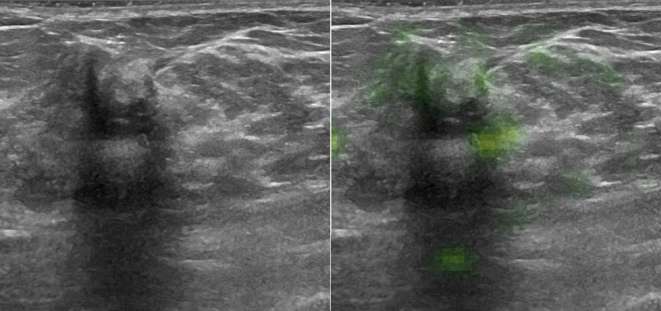

The neural network rated post-operative changes more often as malignant than the human readers (Figure 3), especially in cases with large areas of acoustic shadowing. The differentiation of other features such as size or texture might have led to the few false negatives as illustrated in Figure 4, which shows a quite well defined, small carcinoma with partly well defined granular internal texture. On the other hand, the neural network was excellent and in several cases superior to the readers in correctly classifying small benign lesions (Figure 5) and voluminous malignant lesions (Figure 6). Interestingly, the neural network classified the only lymphoma and the only male patient (Figure 6) correctly in contrast to the two more experienced readers. Notable are also the cases where the neural network classified benign lesions of patients with no prior surgery correctly, even if the images might have had some aspects of post-operative changes (Figures 7 and 8).

A 60-year-old female with a lesion initially rated as BI-RADS 4, later confirmed as biopsy-proven fibrosis of the left breast and 28 months of unsuspicious follow-up. All the human readers rated the lesion as probably malignant (4 or 5/5). Only the neural network classified the lesion correctly as benign (0.38, cut-off 0.69). This is one of the examples where the neural network could have prevented an unnecessary biopsy.